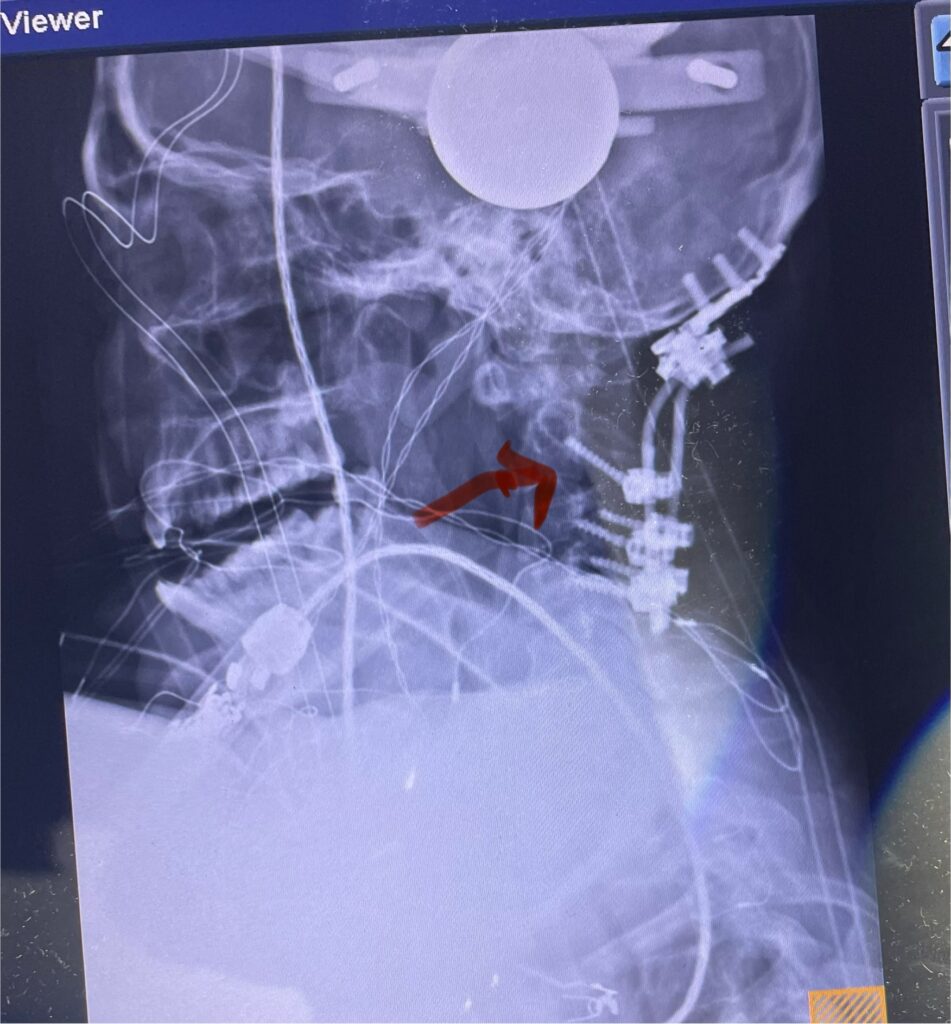

Patients may require an occipital-cervical fusion for both cranio-cervical and atlanto-axial instability, depending on the anatomy. Patients who have long segment posterior cervical fusions can sometimes […]